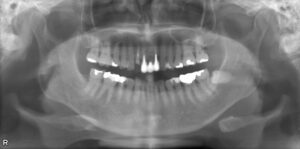

上顎8本欠損症例

BEFORE AFTER 56歳女性/下顎4本欠損/インプラント埋込手術 【治療内容】 神経の処置をしていた歯の状態が悪…